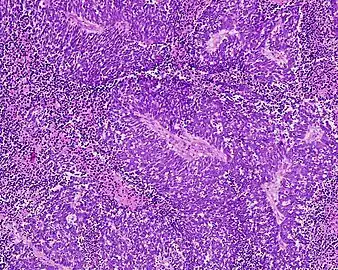

Anaplastic (microcellular, oat cell) carcinoma from the lung (histopathology)

Small-cell carcinoma is an undifferentiated neoplasm composed of primitive-appearing cells. As the name implies, the cells in small-cell carcinomas are smaller than normal cells, and barely have room for any cytoplasm. Some researchers identify this as a failure in the mechanism that controls the size of the cells.[43]